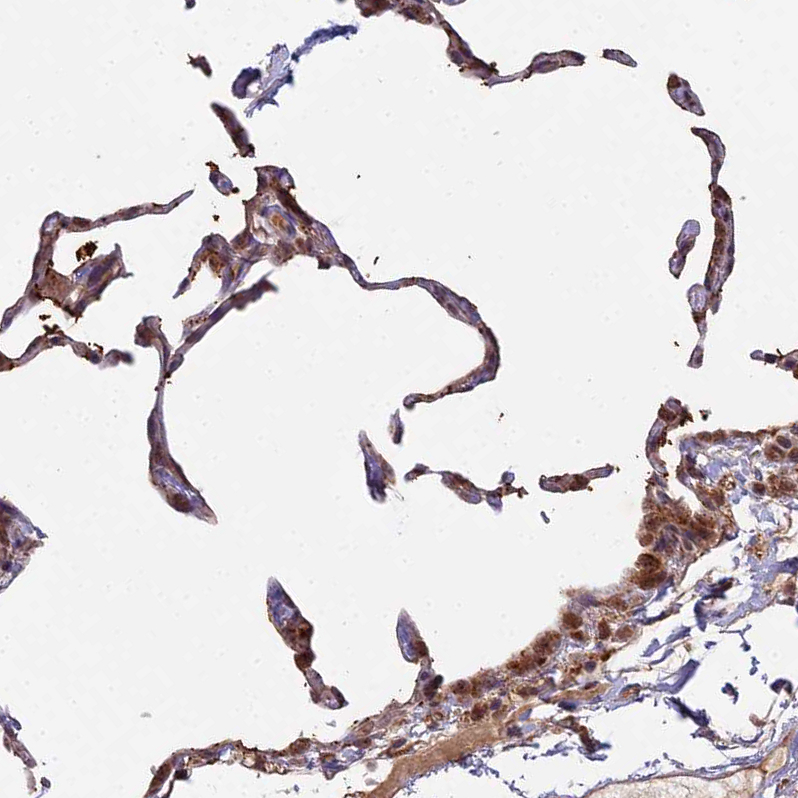

Immunohistochemical staining of human lung shows moderate nuclear and cytoplasmic positivity in pneumocytes.